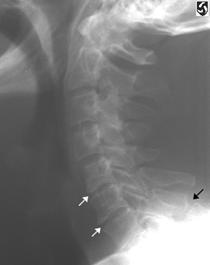

Fractura Jefferson Fractura spanzuratului

Fractura spanzuratului Fractura anterioara C4 Fractura C5 in lacrima in flexie

"in lacrima"